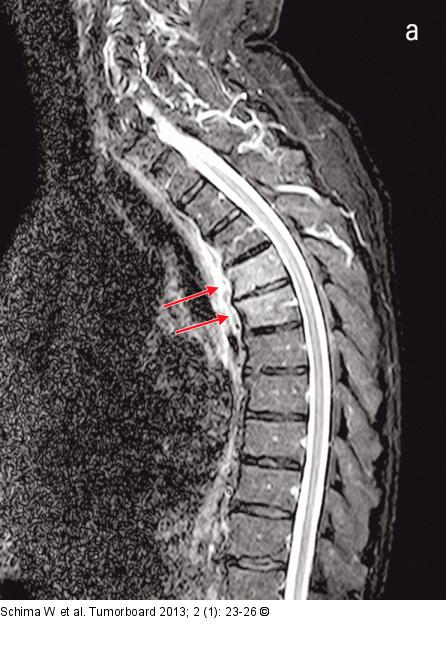

Abbildung 2a-b: Skelettmetastasen MRT der BWS: (a) Es finden sich in der STIR-Sequenz Veränderungen in der Bandscheibe Th 4/5 und ein ausgeprägtes Ödem in den angrenzenden Wirbel Th 4 und 5. (b) Die Kontrastmittelverstärkte Sequenz zeigt einen paravertralen Weichteilanteil (Pfeile), was auch typisch für eine Spondylodiszitis ist |

MRT der BWS: (a) Es finden sich in der STIR-Sequenz Veränderungen in der Bandscheibe Th 4/5 und ein ausgeprägtes Ödem in den angrenzenden Wirbel Th 4 und 5. (b) Die Kontrastmittelverstärkte Sequenz zeigt einen paravertralen Weichteilanteil (Pfeile), was auch typisch für eine Spondylodiszitis ist |